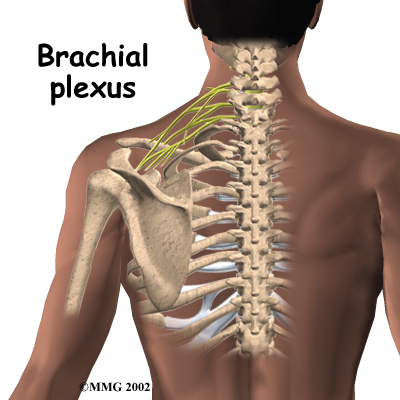

As with any procedure, MUA has risks. There is a very slight chance that the aggressive stretching can injure the nerves of the brachial plexus, which is the network of nerves running to your arm. There is also a risk of fracturing the humerus (the bone of the upper arm), especially in people who have osteopenia or osteoporosis (fragile bones).

As with any procedure, MUA has risks. There is a very slight chance that the aggressive stretching can injure the nerves of the brachial plexus, which is the network of nerves running to your arm. There is also a risk of fracturing the humerus (the bone of the upper arm), especially in people who have osteopenia or osteoporosis (fragile bones).

As with any procedure, MUA has risks. There is a very slight chance that the aggressive stretching can injure the nerves of the brachial plexus, which is the network of nerves running to your arm. There is also a risk of fracturing the humerus (the bone of the upper arm), especially in people who have osteopenia or

As with any procedure, MUA has risks. There is a very slight chance that the aggressive stretching can injure the nerves of the brachial plexus, which is the network of nerves running to your arm. There is also a risk of fracturing the humerus (the bone of the upper arm), especially in people who have osteopenia or